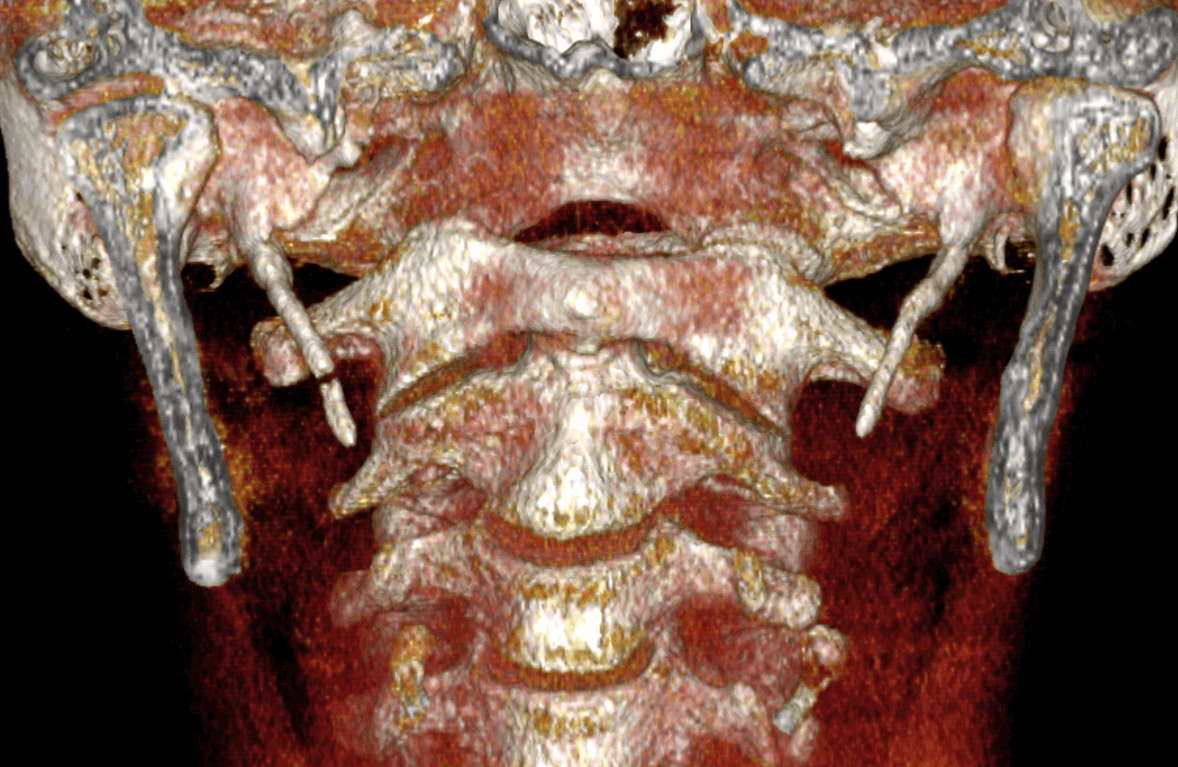

Fig.3

En la representación tridimensional (Fig.3) se observa los signos descritos en las imágenes anteriores en la cual se evidencia en el lado derecho la mineralización segmentada de la apofisis estiloides o la mineralización del tercio superior del ligamento estilohioideo.